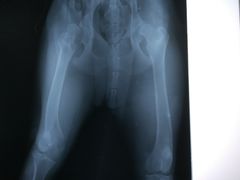

• 骐奇宠物诊疗中心(南亭公路店)

• -骐奇宠物诊疗中心(南亭公路店)

A*果果美妆铺* | 18-05-17

报错